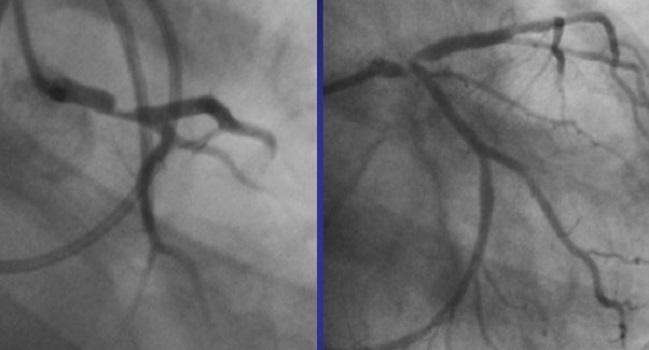

The patients with severe LMS stenosis have a very high risk of major cardiovascular events because of the extent of ischaemic myocardium. It provides oxygenated blood to most of the left ventricle which is the main pumping chamber of the heart. Tapering of the distal left main is also evident in this view.

Ostial involvement of LAD is better appreciated in the previous image. Significant left main stem LMS stenosis is amongst the most feared findings during work-up of suspected coronary artery disease. Left main coronary artery disease.

Left main coronary artery disease LMCAD portends higher prognostic risk as a result of the large myocardial territory at risk ranging from 75 to 100 depending on the dominance of the left coronary circulation. LMCA distal and tight LAD disease RAO caudal view.